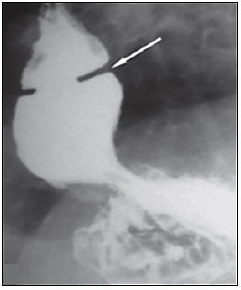

“Um paciente com diagnóstico de doença do refluxo gastroesofágico e queixa de disfagia realizou o seguinte exame contrastado do esôfago:”

Sobre o diagnóstico da imagem, assinale a afirmativa correta.

Qual o diagnóstico mais provável?